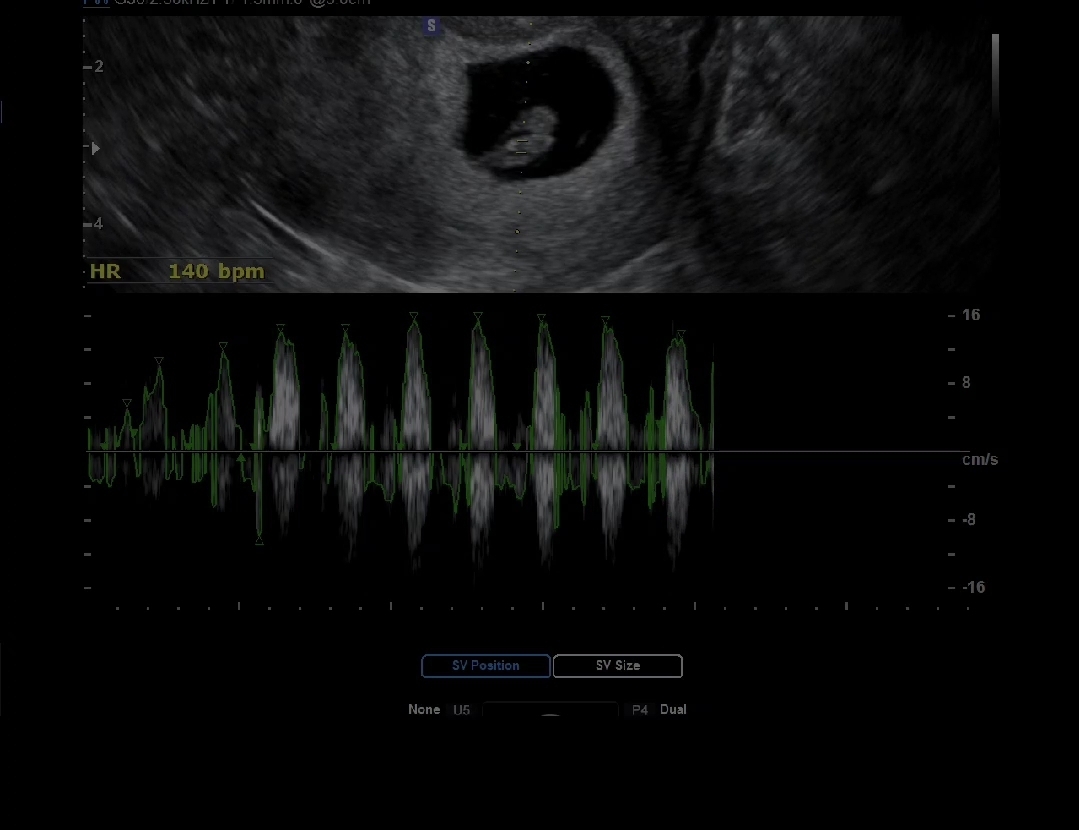

7주 1일 심소 듣고왔어요!!!

지지난 주말에 출혈때매 급히 병원 갔을 때는 심장소리가 안들린다고 걱정스러운 말을 많이 하셨었는데.. 정기 검진 예약한 오늘 병원에서 우렁찬 심장소리 듣고 왔어요❤️ 7주 1일차 139~140bpm 정도라고 해요 너무 행복해요ㅠㅠㅠㅠㅠ!!